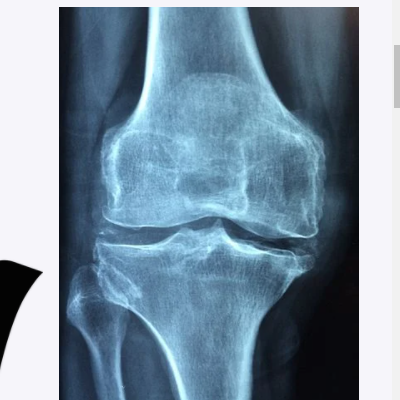

무릎 관절은 세 개의 주요 뼈, 힘줄, 인대 및 연골로 구성된 복잡한 구조이기에 이러한 구조 중 하나와 관련된 부상이나 질병이 원인이 되어 무릎통증으로 나타 날 수 있습니다.

골절

무릎 뼈는 대퇴골, 정강이 및 슬개골로 구성됩니다. 무릎에 외상이 가해지는 경우에 무릎의 슬개골이 부러지거나 갈라질 수 있습니다. 또한 골다공증증의 증상이 있어 약한 뼈를 갖고 있다면 잘못된 자세로 걷거나 발을 딛을 경우 무릎이 골절될 수 있습니다.